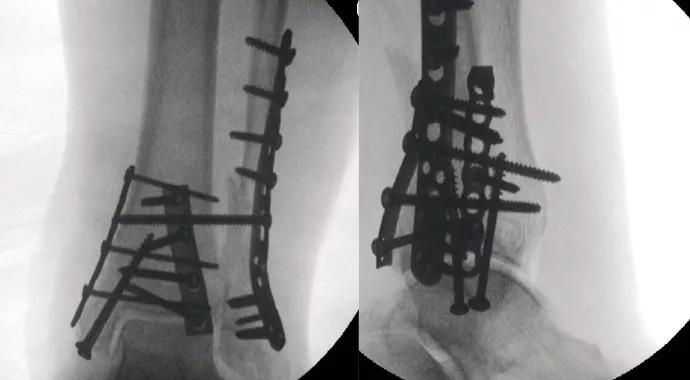

The goal of surgical treatment is to maximize ankle stability (Figure 1). To this end, posterior malleolar fractures are routinely reduced and stabilized with posterior buttress plating through a posterolateral approach. Applying the fibular plate to the posterior or posterolateral surface of the fibula using this same posterolateral incision further enhances construct stability. Anatomically contoured fibular locking plates provide another means of increasing stability, particularly when osteopenia is severe.

Figure 1. (A, B) Injury radiographs showing ankle fracture in a diabetic patient with a history of gastric bypass surgery and kidney-pancreas transplantation on immunosuppressive medications. (C, D) Aggressive and comprehensive internal fixation was performed, including placement of a posterolateral fibular locking plate, posterior and medial buttress plates and a supplementary syndesmotic screw.